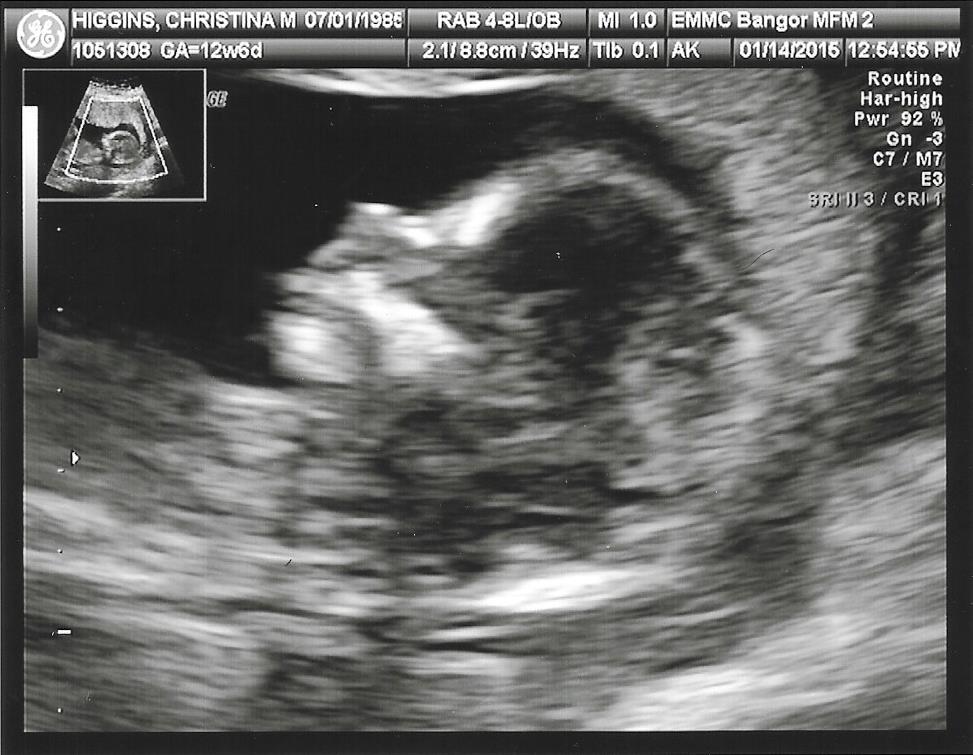

Attachment 23148

Dont think we are seeing the nub here have you got any other shots? Congratulations on baby xx